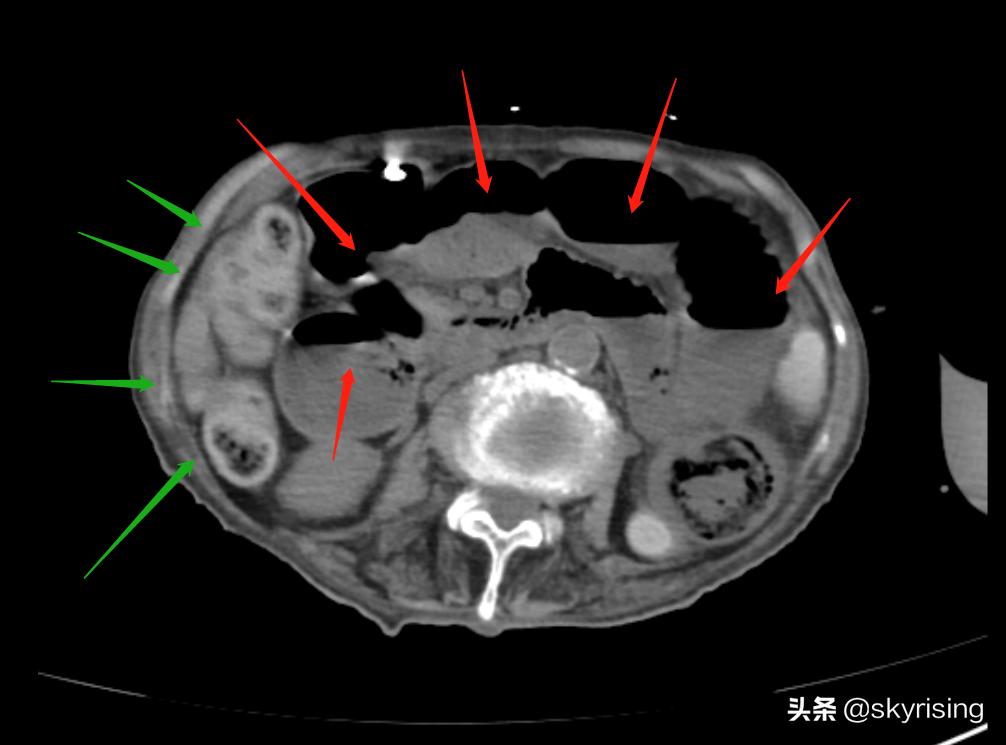

下图红色箭头所示小肠肠管明显扩张、积气、积液,可见梯田状液气平面。这是典型肠梗阻影像表现。

同时可见升结肠肠管管壁环形增厚,密度增高,CT值约85-90Hu,肠管未见扩张。需要警惕,正常结肠管壁密度约50左右,本例如此之高,符合出血,需要警惕血肿可能。

下图绿色箭头所示为主要为横结肠肠管,管壁增厚,密度增高,肠管未见扩张、积气、积液。考虑出血可能。那么还需要考虑的是动脉还是静脉原因引起的出血,如果是动脉栓塞,供血不足肠管管壁增厚、密度减低,中心见层状水肿密度影。静脉栓塞可以是出血性表现,密度增高,血肿外溢等。